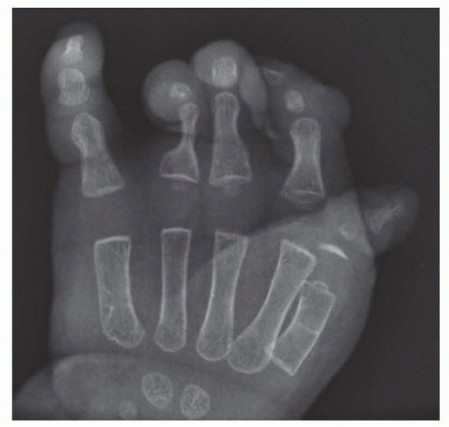

No imaging is required to manage simple bands or bands that are proximal.Plain radiographs are sufficient to evaluate digits when there are multiple digits fused.Typically, only a posteroanterior (PA) view is needed (FIG 3).

Brachysyndactyly Transverse deficiency Apert syndromeVasculocutaneous catastrophe of the newborn (also known asneonatal gangrene,neonatal Volkmann contracture) FIG 3 • PA radiograph of a hand with multiple syndactylized digits due to amniotic band syndrome. Note the compression of the proximal phalanx of the ring and long fingers due to the band. (Courtesy of Shriners Hospital for Children, Philadelphia, PA.)